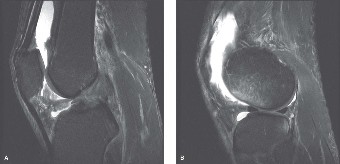

Given the patient's refractory symptoms at the three-month mark and the new onset of localized medial catching, advanced imaging via Magnetic Resonance Imaging (MRI) is indicated to evaluate the soft tissue structures and articular cartilage. MRI provides unparalleled visualization of the chondral surfaces, the medial patellofemoral ligament (MPFL), and the synovial plicae.

The axial T2-weighted fat-suppressed images reveal a thickened, fibrotic medial synovial plica extending from the medial capsule and impinging upon the medial femoral condyle during flexion. There is associated focal bone marrow edema in the medial patellar facet and the opposing medial femoral condyle, representing early chondromalacia patellae (Grade II chondral fissuring). The MPFL is intact with no signs of acute or chronic tearing. The tibial tubercle-trochlear groove (TT-TG) distance is measured at 14 mm, which is within the normal limits (<15 mm is normal, 15-20 mm is borderline, >20 mm is abnormal), suggesting that her maltracking is driven by soft tissue imbalance and dynamic kinetic chain deficits rather than static bony malalignment.